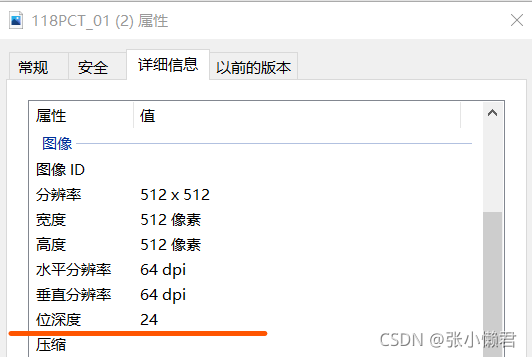

鉴别:

#imageio.imsave()函数将从DICOM文件中读取到的512*512的矩阵转换成--->单通道的灰度图像(512,512)

imageio.imsave("118PCT_01.JPG", img_arr)

#512*512矩阵--->三通道图像(512,512,3)

plt.figure(figsize=(8,8),dpi=64) # 设置图像分辨率位512*512